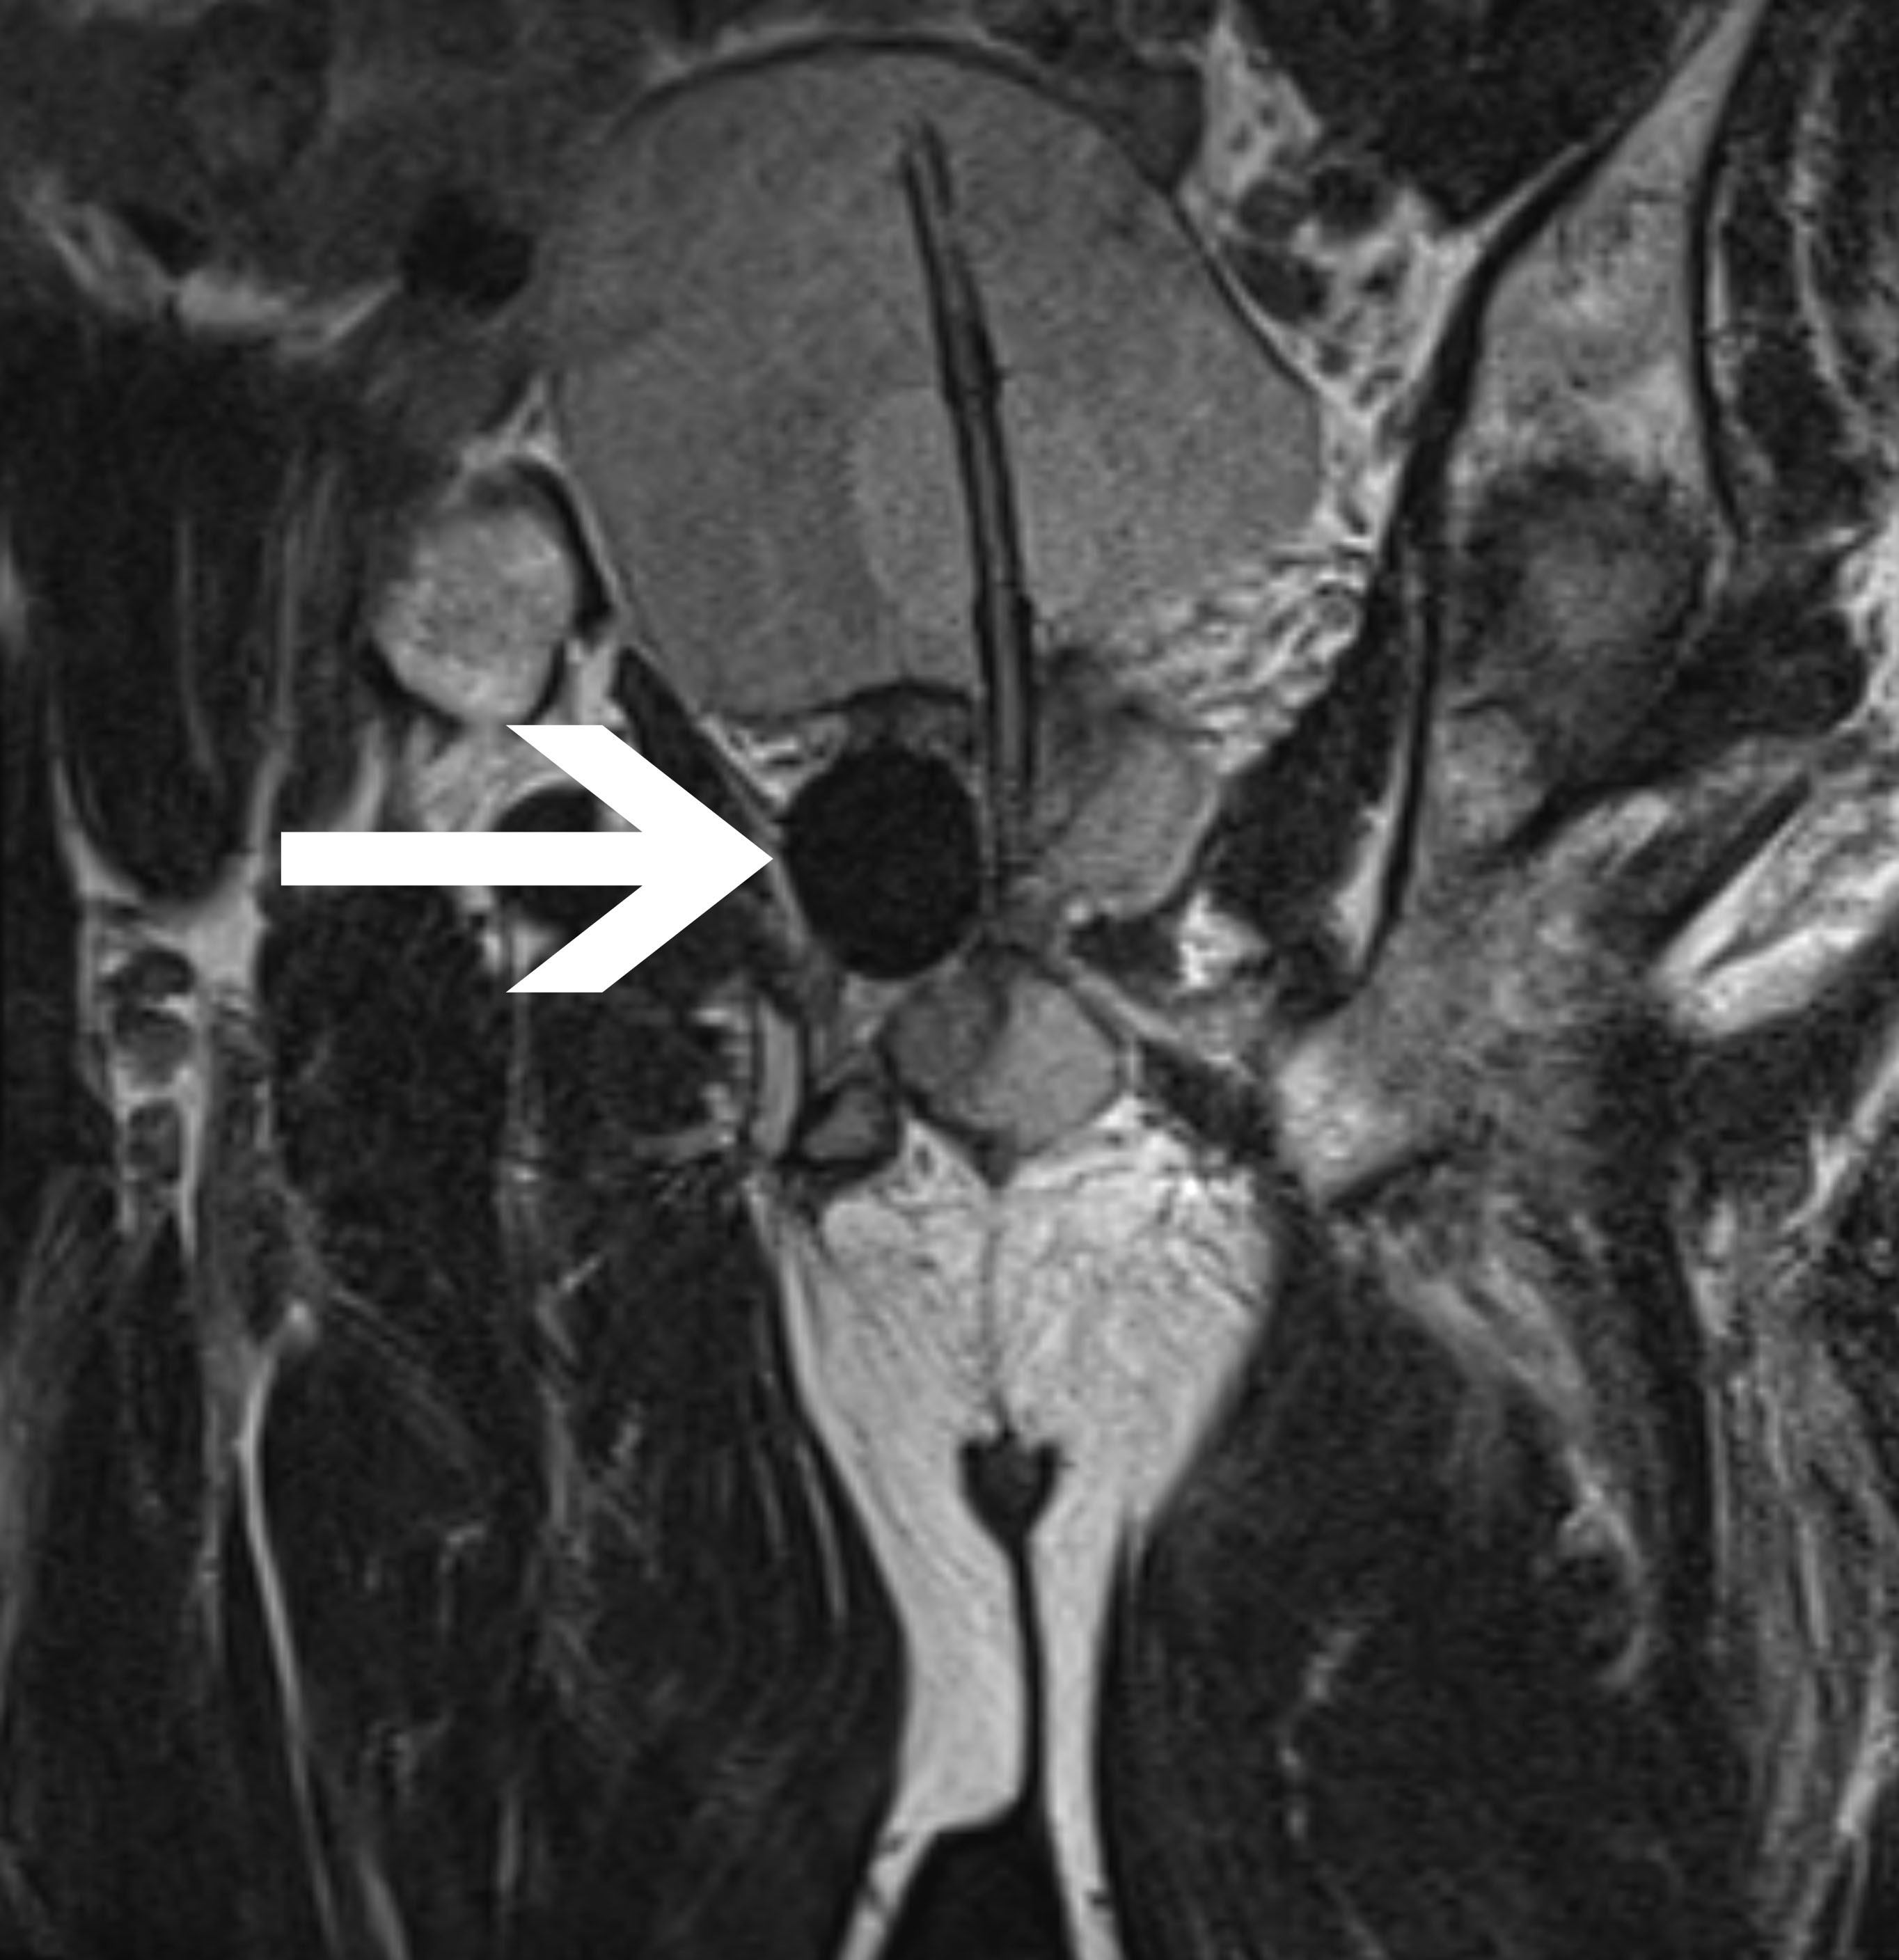

Abb 2:

Periinterventionelles MRT mit

transgluteal positionierten

Kryoablationssonden und dem

anhand des schwarzen

Auslöschungsartefakts erkennbaren

Ablationsareal innerhalb der

Prostata in:

- koronarer Ansicht

- transversaler Ansicht

- sagittaler Ansicht